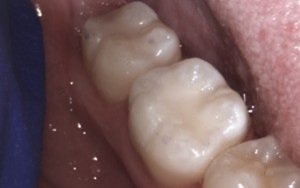

These pictures are a case example of a cosmetic tooth-coloured filling done here at Cornerstone Dental.